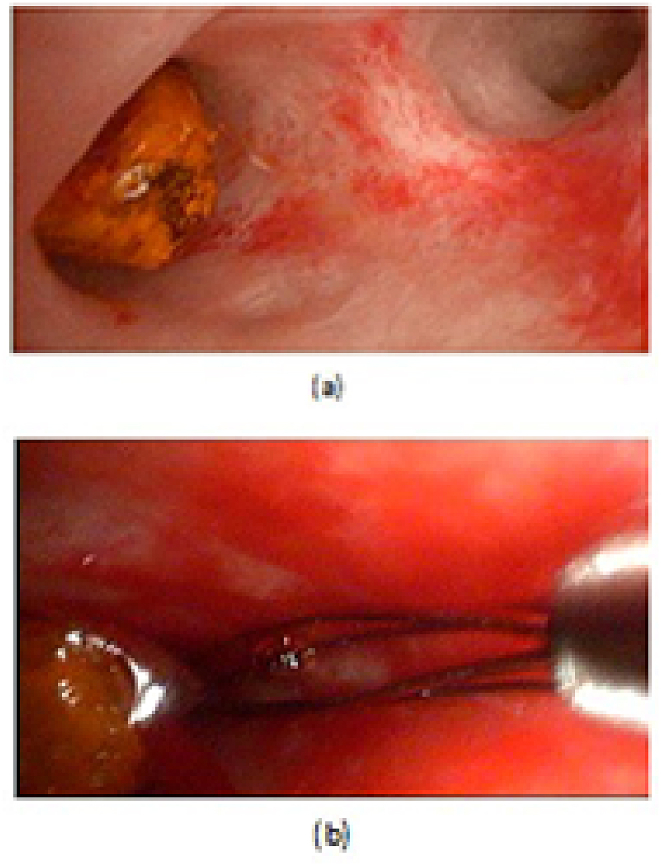

LCD: Under general anesthesia; we used the standard four-port technique of LC. Routine trans-cystic intra-operative cholangiography (IOC) was performed in all cases for identification of stones number, site and size. The gallbladder was left in situ for retraction until the operation was completed. When we reached CBD, a longitudinal supraduodenal choledochotomy(1.5–2 cm) was done using scissors or cautery. The CBD stones were entirely retrieved in all patients using cholecodoscopic extraction techniques (4.5-Fr flexible choledochoscope; Karl Storz, Tuttlingen, Germany) by irrigation, balloon or basket with mechanical lithotripsy when needed. The epigastric port was used to accommodate the operating choledochoscope [ref. 15,ref. 18,ref. [26], ref. [27], ref. [28], ref. [29]]. After all stones were retrieved and clearance of the bile duct was confirmed with choledochoscopy, the choledochotomy was closed with interrupted 4.0 Vicryl sutures in patients with primary closure of CBD and then IOC was done through the cystic duct to confirm absence of stones and leak (Fig. 1). On the other hand, for patients with T-tube drainage, the T-tube was placed in the choledochotomy and secured with sutures, Patients had a cholangiogram on the 6th postoperative day. If the finding was normal, the T-tube was clamped and patients were discharged home with the T-tube in situ then it was removed from 4 to 6 weeks later after normal tube cholangiogram in the outpatient clinic. [ref. 23,ref. 27,ref. 30]. Lastly, laparoscopic HJ was done by 4.0 polydioxanone (PDS) sutures (posterior and anterior interrupted sutures) and a tube drain was placed near the anastomosis and removed days after the operation (Fig. 2) [ref. 1,ref. 14,ref. 31,ref. 32].

OCD: It started by open cholecystectomy (OC) and IOC through the cystic duct; then identification of CBD and the junction between the cystic duct and the CBD were done. A complete Kocher’s maneuver was performed in order to feel the retro- and intra-pancreatic portion of the CBD for easy extraction of stones and to feel the papilla. Then, two stay sutures were placed transversally at the right and left portions of the duct; then the anterior wall of the supraduodenal part of CBD was opened. The incision was performed with a sharp scalpel, then an exploration of the CBD first proximally and then distally with the Randall forceps occurred for extraction of visible stones. The proximal and distal CBD was then irrigated with saline using a soft catheter. In choledochoscopic cases, the CBD stones were entirely retrieved using choledochoscopic extraction techniques (4.5-Fr flexible choledochoscope; Karl Storz, Tuttlingen, Germany) (Fig. 5, Fig. 6). After all stones were extracted and clearance of the bile duct was confirmed; the management was as mentioned in LCD (Fig. 3, Fig. 4). Lastly, in HJ cases, the biliary-enteric anastomosis was done by 4.0 PDS sutures (posterior continuous and anterior interrupted sutures) [ref. 20].